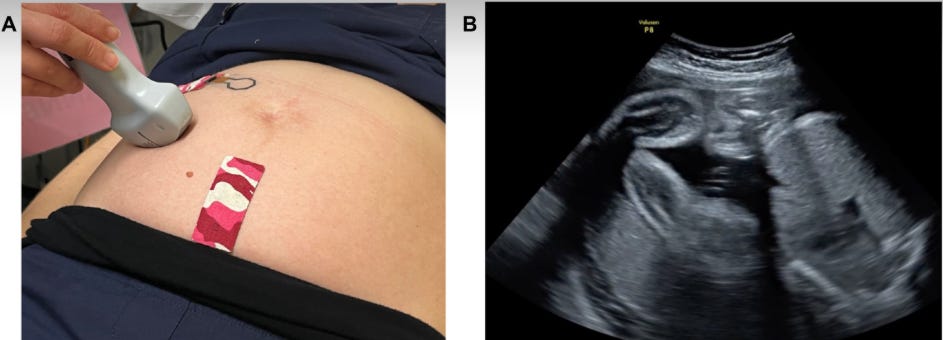

Un patch sans fil permet de surveiller la grossesse à la maison !

Une équipe d’ingénieurs et d’obstétriciens de l’Université Monash a développé un patch portable, fin et discret, qui pourrait transformer le suivi du bien-être fœtal à domicile. Ce dispositif, d’une surface de 10 à 14 cm², détecte avec une précision supérieure à 90 % les mouvements fœtaux, comme les coups de pied ou les étirements, grâce à des capteurs légers et des algorithmes d’intelligence artificielle. Contrairement aux méthodes traditionnelles, souvent subjectives, ce patch offre un suivi continu et non invasif, réduisant le stress des futures mamans.

Testé sur des modèles artificiels et validé lors d’une étude clinique auprès de 59 femmes enceintes, il se révèle prometteur pour détecter précocement les anomalies. Les chercheurs espèrent qu’il complétera les soins obstétricaux standards, offrant aux parents et aux cliniciens des données fiables entre les consultations. Une avancée majeure pour des grossesses plus sereines et mieux accompagnées.